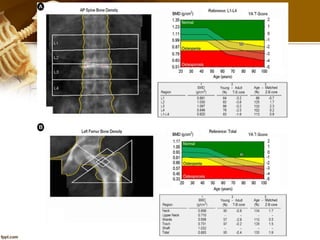

The results of the test are

usually reported as a "T score"

and "Z score.“

But we use T or Z score?

T score

- The T score compares your

bone density with that of

healthy young adult. (30

years)

- A score of 0 means your

BMD is equal to the standard

for a healthy young adult.

Z score

The Z score compares your bone

density with that of other

people of same age, gender, wt

and ethnicity.

A low Z-score (below —2.0) is a

warning sign that you have less

bone mass or that you are losing

bone more rapidly than

expected for someone of your

age.

T & Z score